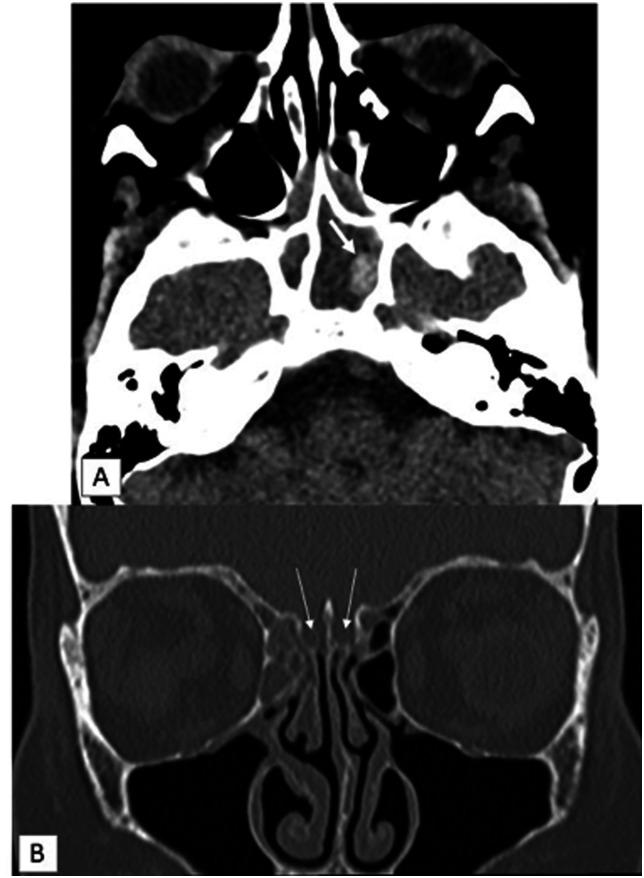

Mucormycosis is an opportunistic fungal infection involving among others the paranasal sinuses, nasal fossa and brain parenchyma. Mucor can invade the brain parenchyma by either contiguous spread from the paranasal sinuses or through vascular invasion. We report a case of fatal rhino-cerebral mucormycosis in whom cytotoxic edema at magnetic resonance diffusion-weighted imaging was symmetrically restricted to both neocortical and paleocortical primary areas of olfactory projection at earliest phase of the disease process. Shortly later tissue damage extended into the whole brain. This undescribed observation raised the hypothesis of preferential way of brain invasion by Mucor through the olfactory tract.